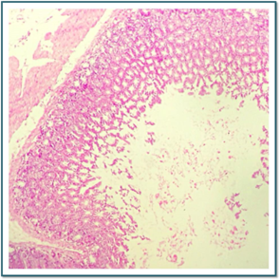

Láminas de Histología

Description

Laboratorio de histología, Bibliografía Ross Pawlina 5ta Edición.